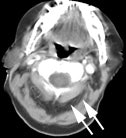

Genitourinary activity: The image below demonstrates activity within the collecting system of a transplanted kidney (black arrows). This should not be mistaken for an abnormality. |

Bladder cancer: Dilute urinary activity in this patient's bladder allowed accurate detection of their bladder cancer (white arrows on CT, black arrows on PET scan). In general, urinary excretion of FDG limits evaluation of urinary tract malignancies, however, hydration and diuresis can improve diagnostic accuracy. |